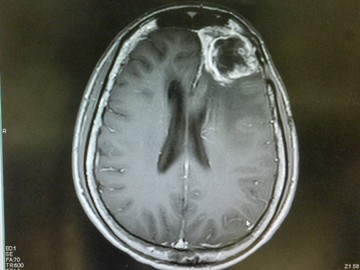

Megvan a leghalálosabb agyrák ellenszere? Nézze meg, mit talált a kínai-amerikai kutatócsoport